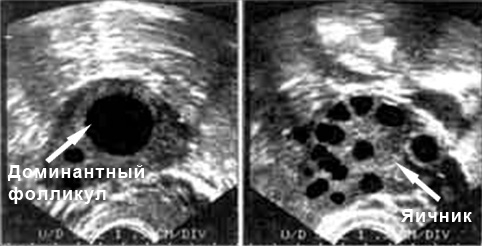

Признаки овуляции на УЗИ

Как врач может определить, что овуляция состоялась? На экране ультразвукового аппарата появятся признаки, подтверждающие выход яйцеклетки.

- На третьем визите к специалисту были выявлены созревающие фолликулы;

- зафиксирован разрыв фолликула;

- за маткой было обнаружено скопление жидкости;

- после разрыва фолликула УЗИ показало увеличение желтого тела;

- отсутствие доминантного фолликула является одним из основных признаков овуляции.

Расшифровка результатов

Все результаты будет интерпретировать квалифицированный специалист. Он знает нормы показателей для каждого этапа цикла и анализирует отклонения от этих норм. Ниже представлены нормы, которые можно сопоставить со своими результатами, чтобы понять, есть ли проблемы с овуляцией.

- Фаза роста фолликула.

- 1-8 день: доминантный фолликул отсутствует;

- 8-12 день: на УЗИ он виден, размер составляет 10 мм;

- 12-14 день: размер достигает 15 мм;

- 14-15 день: это период перед овуляцией, когда фолликул достигает 21 мм.

- Овуляция:

- В фолликуле наблюдается яйценосный бугорок;

- Стенка фолликула утолщается;

- После овуляции фолликул больше не определяется;

- За маткой может быть немного жидкости.

- Лютеиновая фаза – это процесс формирования желтого тела. Если зачатие произошло, его размер составит 18 мм. Если он превышает 23 мм, это может указывать либо на беременность, либо на наличие фолликулярных кист.

- Менструация. На УЗИ видны небольшие фолликулы, которые едва достигают 8 мм.